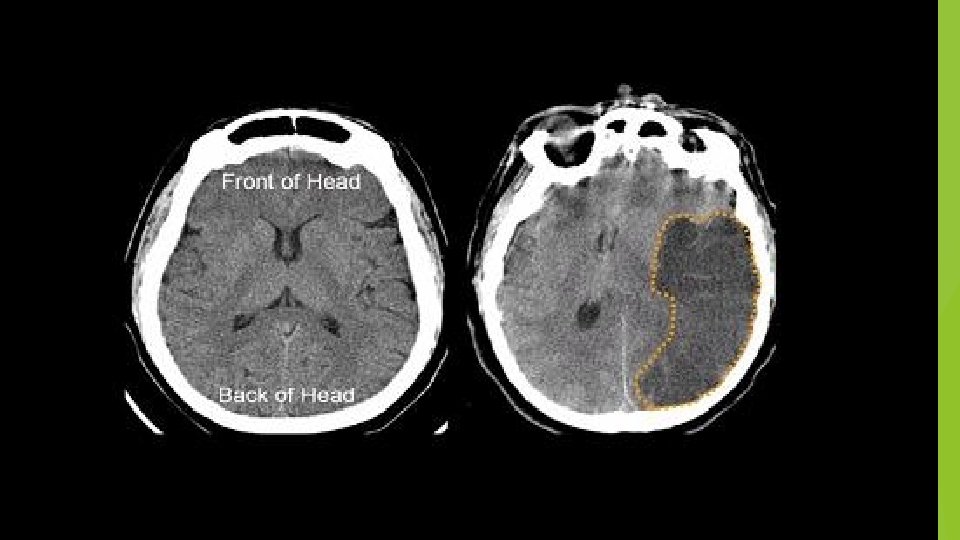

IMAGING CT…reliable for intracranial hemorrhage close to 100% sensitive not sensitive for ischemic CVA…especially early MRI…diffusion weighted hyperdense regions of ischemia can detect ischemia after 5 -10 minutes time consuming…. cooperation issues ECHO…echocardiography can identify source of cerebral emboli identify patent foramen ovale

rt. PA {Alteplase} With normal or early ischemic change on imaging If frank hypodensity >1/3 MCA no rt. PA Unclear use…mild deficits improving CVA symptoms surgery< 3 months recent MI Maybe harmful in pts on dabigatran, apixaban, rivaroxiban Other lytics…not recommended (streptokinase) or investigational